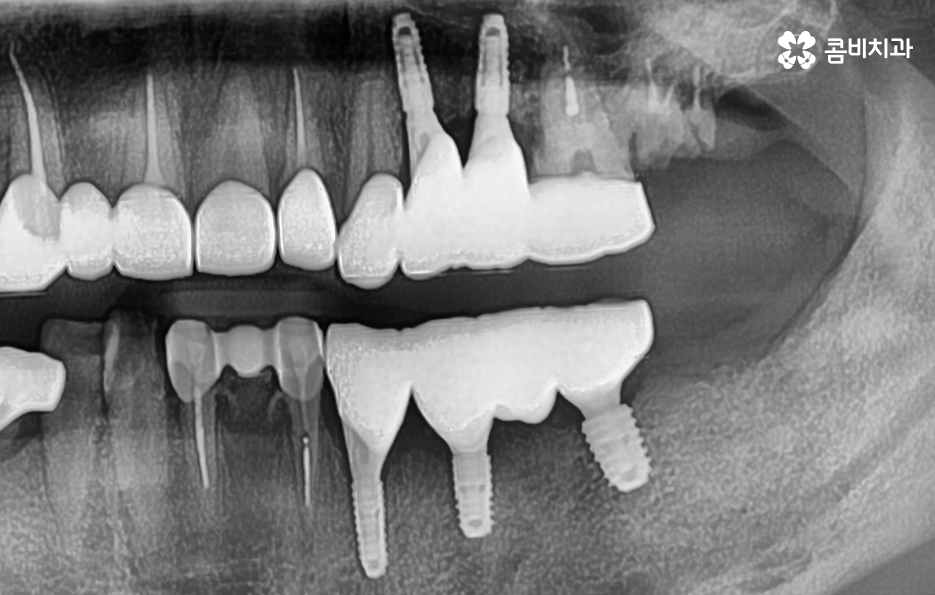

위 사진을 보시면 치아를 이미 잃은지 시간이 지난 상태의 치조골 즉 잇몸 뼈의 상태인 부위도 있고 어떤 치아는 거의 뿌리 부분만 남아 있으며 어떤 치아는 여러개의 보철물이 이어져 있는 상태인 경우도 있는데요

엑스레이 상태만 봐도 치아 저작 기능이 상당히 저하되어 있고 치아 상태가 매우 좋지 않음을 느낄 수 있을 정도인데 사실 임플란트를 필요로 하는 환자분들의 상당 수는 50대 이후부터 노년기에 치아 상실로 인한 임플란트의 필요성을 절실하게 느끼시는 분들이 많고 이미 여러 이유들로 인해 치아도 많이 발치된 경우도 있고 발치를 해야할 상황에서 임플란트를 알아보시는 분들이 많이 있어요

우리가 흔히 치아의 수명이 다했다고 판단하는 기준에서 치아의 뿌리 쪽 상태를 매우 중요하게 보고 있는데 치아의 구조에서 신경조직의 손상은 신경치료 후 크라운을 씌워서 보존 치료가 가능하지만 충치가 심하거나 충치가 뿌리까지 진행되어 심하게 손상된 경우에는 결국 발치하게 되는 것처럼 임플란트의 치료 원리는 잇몸 뼈에 임플란트의 인공치근을 식립하여 잇몸 뼈와의 골유착 과정을 통해 이름 그대로 인공치아의 역할을 수행하게 되기 때문에 임플란트의 인공치근이 잇몸 뼈가 안정적으로 골유착이 되는 것이 임플란트 치료의 관건이 될 수 있어요

따라서 자연치아로 따지면 치아 뿌리의 역할을 하는 것이 잇몸 뼈에 식립된 임플란트의 인공치근이 그 역할을 하고 있기 때문에 특히 어금니 처럼 저작력에 있어서 중요한 치아 부위에 임플란트를 식립할 경우에는 저작력을 감당하기 위해 그만큼 잇몸 뼈의 상태가 충분해야 하는데 잇몸 뼈의 두께와 깊이, 골질이 충분히 확보된 상태에서 임플란트를 식립해야 하므로 잇몸 뼈가 부족한 경우에 뼈이식을 추가적으로 진행하고 있어요